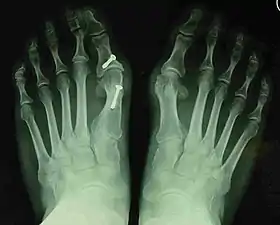

- For severe bunion deformity correction (Fig. 7)

- For recurrence correction after osteotomy procedure (Fig. 8)

Late deformity recurrence can happen after osteotomy (bone-breaking) procedures because osteotomy surgeries do not specifically stabilize first metatarsal bone.